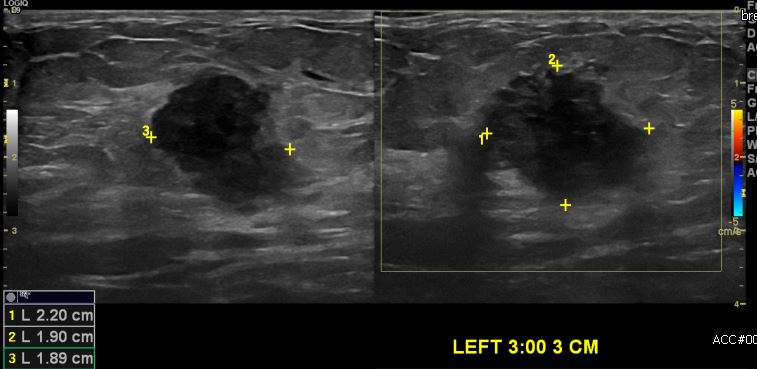

상기환자 좌측유방에 만져지는 멍울있어 내원하신 50대 여성분으로 좌측 3시 방향에서

3cm 떨어진 거리의 멍울 조직검사 시행하여 좌측 침윤성 유관암 진단 되었습니다.